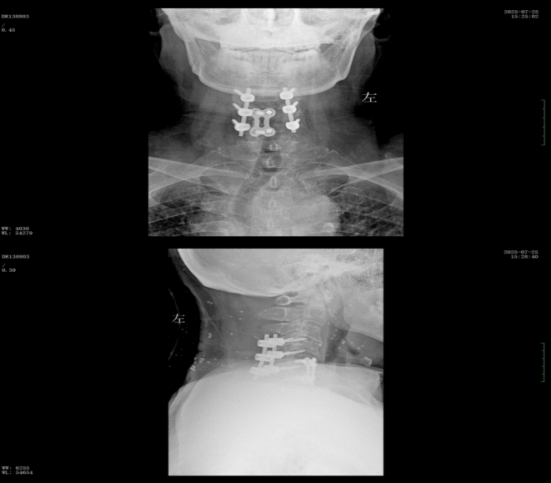

該患者此前因膽囊結(jié)石祁東縣人民醫(yī)院治療,來自衡陽市中心醫(yī)院駐該院副院長李攀峰為其主刀進行手術(shù),術(shù)后患者恢復(fù)良好。后因突發(fā)四肢癱瘓、生活無法自理,為尋求進一步治療,經(jīng)醫(yī)聯(lián)體通道轉(zhuǎn)入衡陽市中心醫(yī)院。脊柱外科錢軍博士團隊接診后,迅速組織詳細問診、體格檢查及系統(tǒng)術(shù)前評估。查體顯示患者四肢關(guān)鍵肌肌力僅I級,感覺功能明顯減退,結(jié)合影像學(xué)結(jié)果,診斷為頸脊髓損傷伴不全癱,有明確手術(shù)指征。

術(shù)前核磁共振提示:頸椎椎管狹窄、頸脊髓信號改變